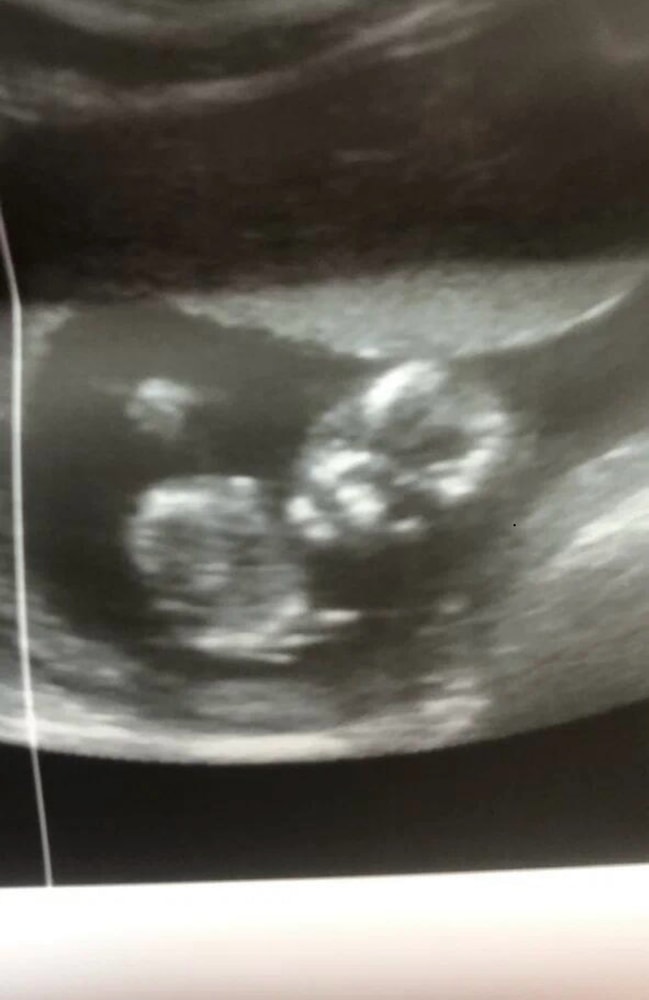

Сходила в частную клинику на УЗИ в 28 недель, сказали, что всё хорошо ттт, и дали фото. И вот когда я уже вышла с клиники и увидела фото, я вообще ничего не поняла. Это вроде голова, но вообще непонятно что где и выглядит жутковато...

Может тут кто-то разбирается или понимает что где на этих фото?

Просто не самый удачный ракурс распечатали вам, не бойтесь)

Я понимаю, что это череп. Но, с какого ракурса понять не могу🤣

На последнем фото,под круглым тёмным пятном,белая полоска -глаз(веко закрыто) ну и профиль видно,рука правая приподнята.Ну я так увидела 😃 У меня тоже ни одной нормальной фотки не было с узи,лежал как то не удобно и руками ,ногами закрывался

Голова и ручки около лица. Голова у них на узи со всем содержимым видна🤣, потому и жутковато выглядит🤣🤣🤣